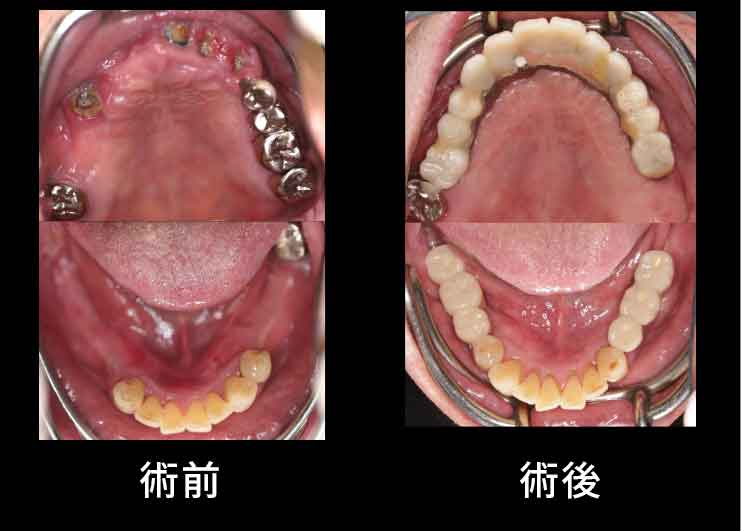

Case2. 68歳男性

下歯槽神経近くにインプラントを埋入したケース。

歯を失った下あごの骨が大きく吸収し、下歯槽神経の出入り口であるオトガイ孔が表面に近い部分に出てきています。そこで、X-ガイド使用により、下歯槽神経を避けた手術を行いました。

インプラントでしっかり噛めるようになったことで筋肉がしっかりし、お肌にもハリが出て、若々しさを取り戻されました。

五十嵐歯科ではこのように、表情筋の回復まで考慮した治療を行います。